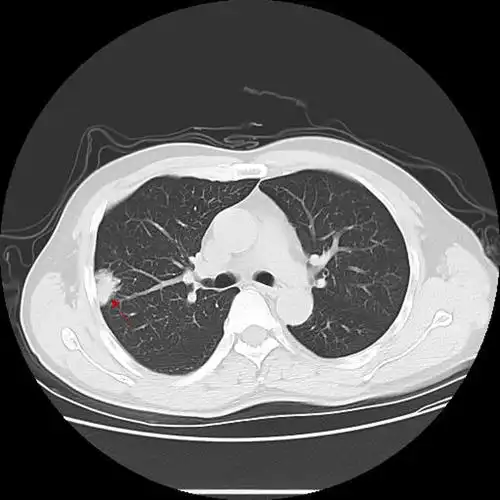

ct诊断肺癌伴有多发转移怎么办?有可能出错吗?还能手术吗?